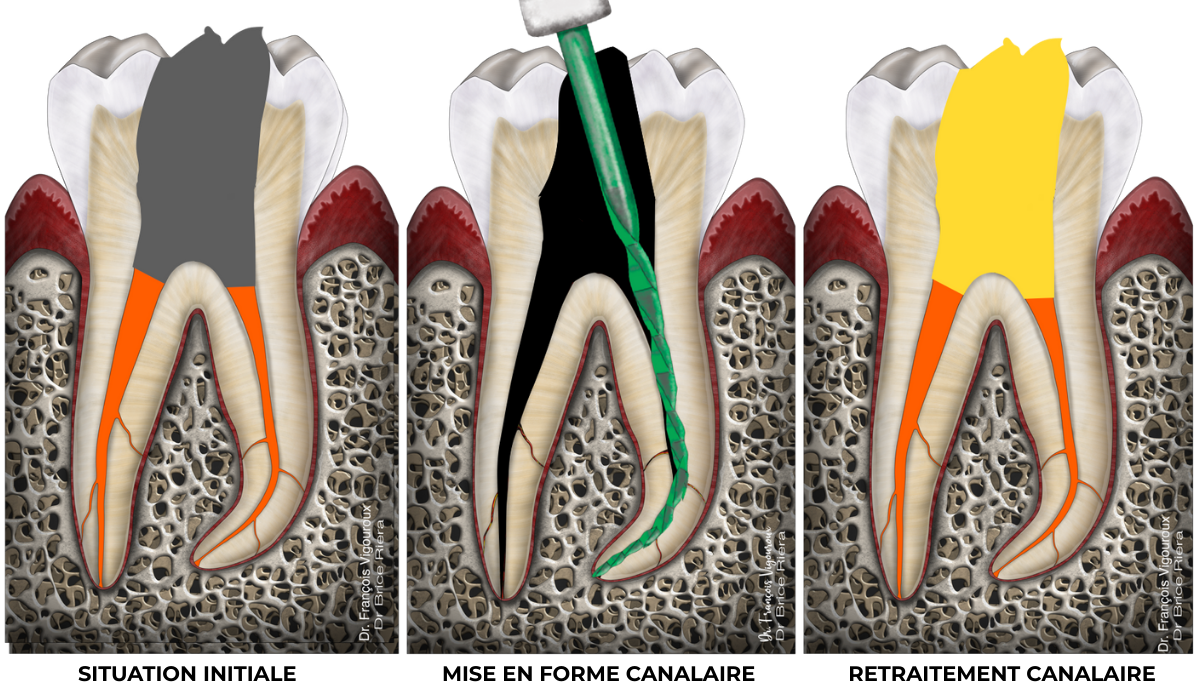

Retraitement canalaire

Une dent peut d’ores et déjà avoir bénéficié d’un traitement canalaire. Pour autant celui-ci doit être effectué de nouveau. C’est le retraitement canalaire.

Quelques exemples de raisons pouvant expliquer la reprise d’un retraitement canalaire :

- Une nouvelle restauration ou prothèse (inlay, onlay, couronne etc..) est prévue.

De la même façon qu’une maison nécessite un assainissement de ses fondations avant reconstruction, une dent nécessite un retraitement canalaire lorsqu’une nouvelle prothèse est indiquée. Ceci, qu’une lésion apicale soit présente ou pas.

- Une infection intra-canalaire est présente malgré le traitement canalaire déjà en place, et provoque une lésion apicale.

Cas clinique

Retraitement canalaire : 80-95% de taux de succès